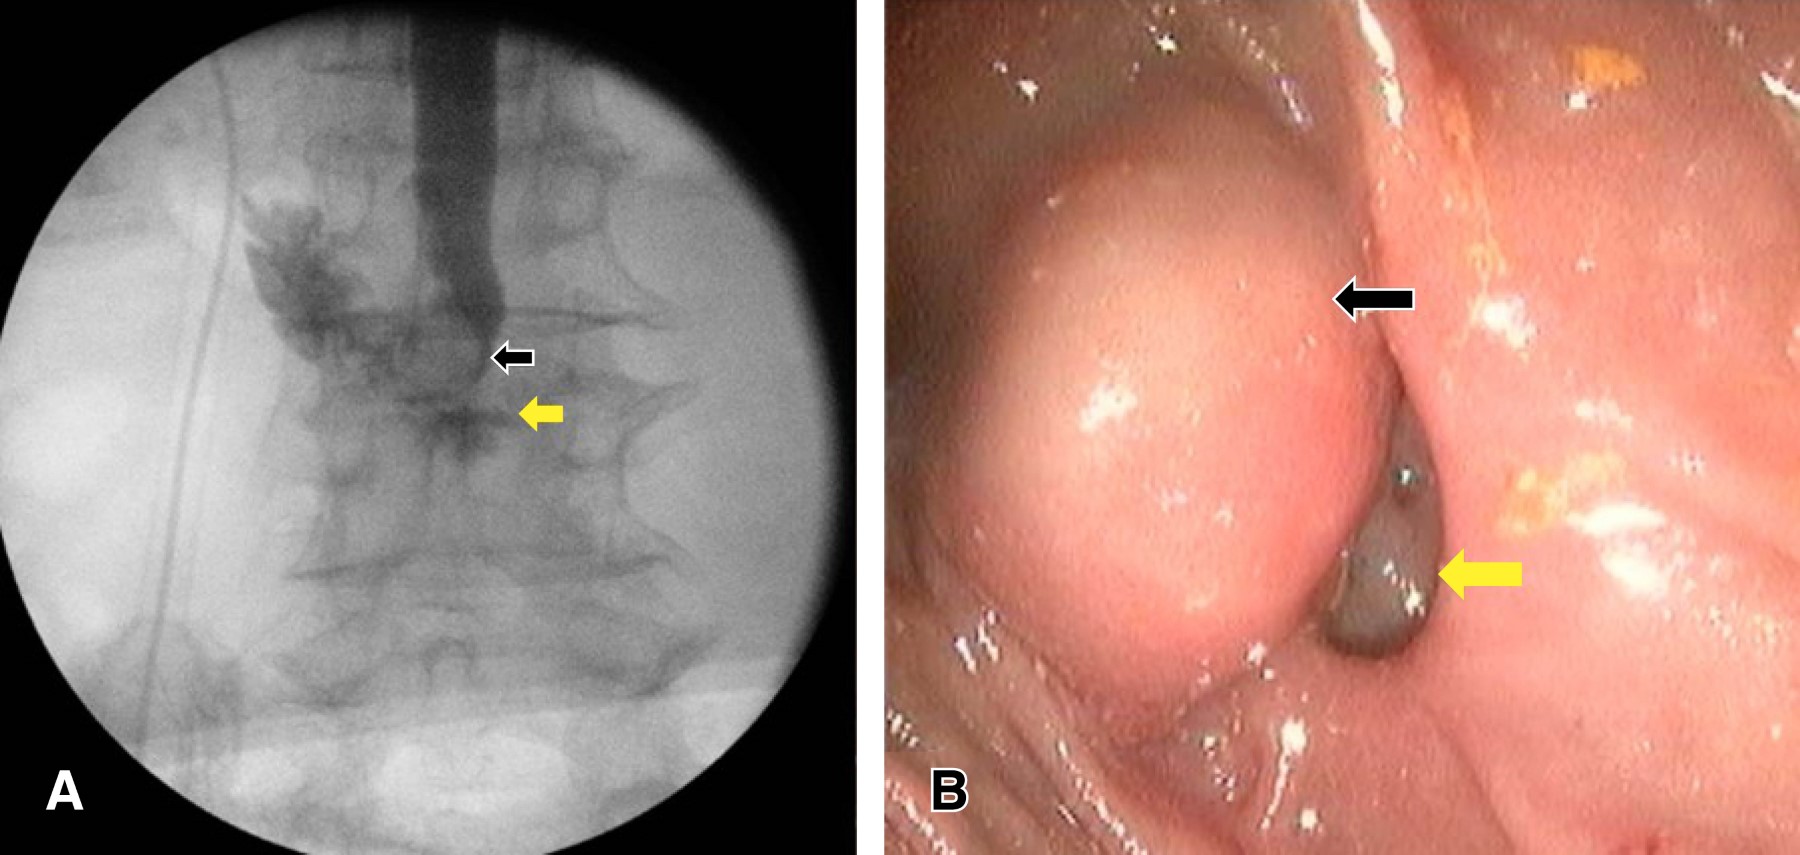

Primer caso clínico. Paciente femenino de 70 años con cuadros recurrentes de dolor abdominal, de 10 años de evolución, en epigastrio y sensación de plenitud gástrica, acompañada de emesis gastro-biliar, quien recibió tratamientos para dispepsia y cólico biliar que no fueron eficaces. Fue abordada previamente sin alteraciones por imagen y bioquímicos. Durante su abordaje diagnóstico sin ictericia, signo de Murphy y puntos pancreáticos negativos, con dolor abdominal epigástrico a la palpación profunda; paraclínicos con hiperbilirrubinemia a expensas de bilirrubina directa (BT 2.3 mg/dL, BD 1.60 mg/dL) y patrón colestásico (FA 220 U/L, GGT 316 U/L), sin leucocitosis (7.4×103/µL). Se realizó ultrasonido con datos indirectos de coledocolitiasis (colédoco de 16.5 mm), se solicitó colangiorresonancia magnética concluyente con coledocolitiasis y divertículo duodenal (Figura 1). Se efectuó intervención quirúrgica con colangiografía y CPRE transoperatoria, con extracción de lito impactado en papila duodenal, así como realización de esfinterotomía, encontrando divertículo duodenal a 2.5 cm de la papila de Vater (Figura 2), sin complicaciones, con mejoría evidente de dolor abdominal, por paraclínicos sin anormalidades. Se logró el egreso de la paciente y al seguimiento consecutivo no hubo anormalidades.

Segundo caso clínico. Paciente femenino de 86 años con cuadro de dolor abdominal intermitente en epigastrio y mesogastrio de larga evolución, con sensación de plenitud gástrica, sin otra sintomatología agregada, recibió diversos tratamientos por síntomas de gastroenteritis y enfermedad ácido-péptica, pero fueron ineficaces. Durante su abordaje diagnóstico sin ictericia, signo de Murphy y puntos pancreáticos negativos, con dolor abdominal a la palpación profunda en hipocondrio derecho y mesogastrio; paraclínicos dentro de parámetros normales. El ultrasonido mostró dilatación de vías biliares intrahepáticas y colédoco de 12 mm, sin evidencia de litiasis vesicular ni en colédoco. Se realizó duodenoscopía y CPRE encontrando DDY de 3 cm aproximadamente con restos alimenticios abundantes en su interior, los cuales se retiraron bajo lavado con solución estéril (Figura 3). El procedimiento se llevó a cabo sin complicaciones, paraclínicos sin anormalidades; se egresó y se dio seguimiento consecutivo con duodenoscopía, evidenciando DDY sin restos alimenticios ni datos de inflamación.

Figura 2

Figura 3